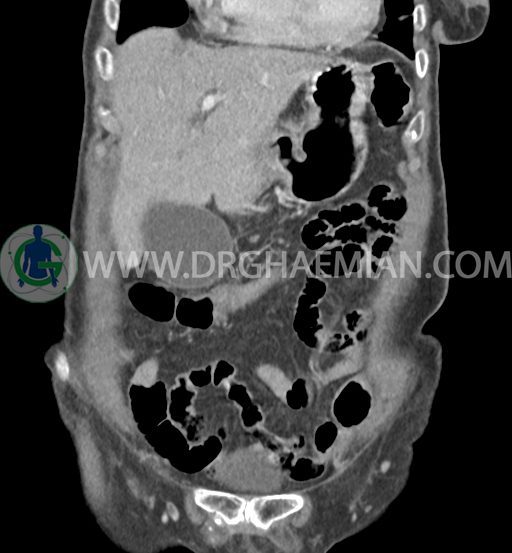

سی تی اسکن شکم و لگن با استفاده از اشعات ایکس تصاویر عرضی از ناحیه شکم و لگن ایجاد میکند. در این کیس سرطان مجرای صفراوی (کولانژیوکارسینوما)، توده در کبد، کیست کورتیکال در کلیه چپ، کلسیفیکاسیون دیواره آئورت و … دیده می شود.

در سی تی اسکن اسپیرال شکم و لگن با و بدون کنتراست خوراکی و وریدی (مولتی دیدکتور 16 با مقاطع ظریف و بازسازی های ساژیتال و کرونال) :

ضایعه ای در معده ، روده باریک و کولون مشهود نیست .

تصویر شبیه به توده به قطر 15mm بین خم کبدی کولون و سگمان 6 کبد و قطب تحتانی کلیه راست و به قطر 8mm در انتریور سکوم مطرح کننده توده های peritoneal